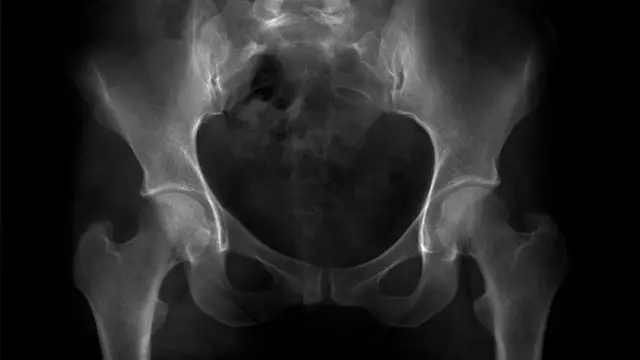

நாம் சுமார் 2.5 கோடி ஆண்டுகளுக்கு முன்பு நமது வாலை இழந்தோம். அதன் பரிணாம எச்சமாக நாம் இன்னும் கோசிக்ஸ் (coccyx) என்று அழைக்கப்படும், நமது முதுகுத்தண்டின் கீழ்முனையில் இருக்கும் ஒரு சிறு முக்கோண வடிவிலான எலும்பினைச் சுமக்கிறோம்.

நமக்கு வால் எலும்பு ஒரு பரிணாம எச்சமாக இருப்பதைப் போலவே, வால் இல்லாததை உறுதிப்படுத்தும் மரபணுவின் மாற்றத்திற்கு ஸ்பைனா பிஃபிடாவை நோய் ஒரு அரிய தொடர்ச்சியாக இருக்கலாம் என்று இந்த ஆராய்ச்சிக் குழு கருதுகிறது.